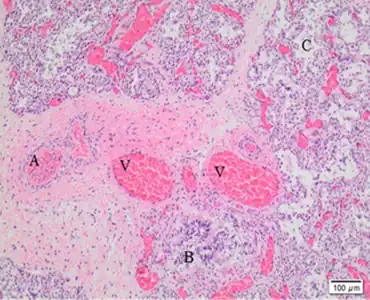

| Dilated capillaries are not in contact with alveolar epithelium | |

ACD is typically diagnosed by examination of lung tissue under a microscope, either from lung biopsy or an autopsy. The characteristic findings of misplaced pulmonary veins adjacent to pulmonary arteries, and abnormal alveolar and capillary development confirm the diagnosis.[1] FOXF1 genetic testing is also available, which can confirm the diagnosis without invasive testing.[2] There are no effective treatments for severe ACD. Standard therapy, which includes mechanical ventilation, pulmonary vasodilators, and possibly ECMO, provide only temporary improvement in symptoms with disease progression returning within hours. For babies with atypical ACD, response to medical therapy is more sustained, lasting for several months. For those that can be stabilized, definitive treatment is bilateral lung transplantation.[1]

How mutations affecting FOXF1 or its regulatory region cause ACD is unknown. ACD-causing mutations result in abnormal development of lung vasculature and alveoli. In ACD, the interstitium of alveoli is thickened, with few to no capillaries located at the alveolar surface to perform gas exchange, and with lower capillary density overall. This reduction in capillaries and their misplacement away from the alveolar surface result in poor oxygenation and retention of carbon dioxide in the blood and high pulmonary blood pressure.[1] There is also evidence of direct connections between pulmonary arteries and systemic vessels, which would deliver deoxygenated blood to the body, also contributing to low blood oxygenation.[4]

Another characteristic histologic finding is the presence of a pulmonary vein located next to a pulmonary artery and bronchus in the same bronchovascular bundle. In a normal lung, the pulmonary vein courses with lymphatic vessels in the lung septa.

The gold standard for ACD diagnosis is by examination of lung tissue under a microscope. The diagnosis is made if the pathologist sees the characteristic findings of ACD: misplaced pulmonary veins adjacent to pulmonary arteries, abnormal alveoli with thickened interstitia and abnormal capillary development. Due to the rapidly progressive course of ACD, this diagnosis is frequently made during autopsy. If ACD is suspected early, examination of tissue from lung biopsy results in the quickest diagnosis.[1] Genetic testing for FOXF1 is now available and can allow for slower but non-invasive diagnosis. As not all disease-causing mutations are known, false negatives or results of uncertain significance are possible with genetic testing.[2]